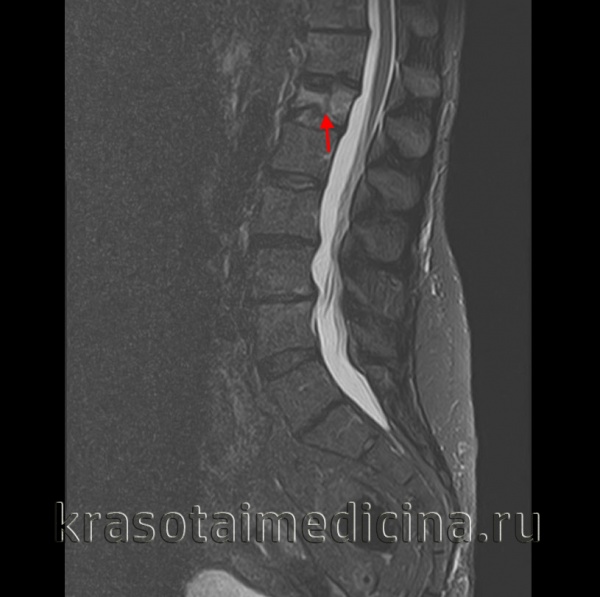

4. МРТ при компрессионном переломе позвонка с передней компрессией:

• Линия перелома характеризуется низкой интенсивностью сигнала во всех режимах исследования:

о В STIR режиме линия перелома может экранироваться участком отека костного мозга

о Морфология перелома соответствует таковой, описанной в КТ-исследовании

• Участки отека костного мозга в виде тяжей, окружающих линии перелома:

о Низкая или промежуточная интенсивность сигнала в Т1 -режиме

о Высокая интенсивность сигнала в Т2 и STIR режимах

• Гематома паравертебральных тканей, которая может напоминать опухолевое поражение

• Зоны перелома, отека костного мозга и паравертебральной гематомы усиливают сигнал при контрастировании гадолинием

(Слева) На сагиттальном Т1-ВИ определяется чашеобразное вдавление верхней замыкательной пластинки позвонка у пациента с остеопорозом. Линия перелома, характеризующаяся низкой интенсивностью сигнала, расположена сразу же под замыкательной пластинкой. Пациенты с остеопорозом часто отмечают острое начало болевого синдрома после минимальной травмы либо вообще при отсутствии таковой.

(Справа) STIR МР-И: взрывной перелом Т12 и компрессионные переломы Т10 и Т11. При компрессионных переломах задняя покровная пластинка остается интактной.